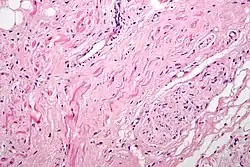

Гистология

Атипичные мышечные волокна сердца — это специализированные проводящие кардиомиоциты, богато иннервированные, с небольшим количеством миофибрилл и обилием саркоплазмы[B: 5].

Синусовый узел

Клетки, составляющие синусовый узел, гистологически отличаются от клеток рабочего миокарда. Хорошим ориентиром служит выраженная a.nodalis (узловая артерия). Клетки синусового узла по размерам меньше клеток рабочего миокарда предсердия. Они группируются в виде пучков, при этом вся сеть клеток погружена в развитый матрикс. На границе синусового узла, обращенной к миокарду устья верхней полой вены, определяется переходная зона, которая может расцениваться как присутствие клеток рабочего миокарда предсердий в пределах синусового узла. Такие участки вклинения клеток предсердия в ткань узла чаще всего встречаются на границе узла и пограничного гребня (выступа стенки правого предсердия сердца, которым заканчиваются вверху гребенчатые мышцы)[1].

Гистологически синусовый узел состоит из т. н. типичных клеток узла. Они располагаются беспорядочно, имеют веретенообразную форму, а иногда разветвления. Для этих клеток характерно слабое развитие сократительного аппарата, случайное распределение митохондрий. Саркоплазматический ретикулум развит хуже, чем в миокарде предсердий, а система T-трубочек отсутствует. Это отсутствие, правда, не является критерием, по которому выделяются «специализированные клетки»: часто система T-трубочек отсутствует и в рабочих кардиомиоцитах предсердия.

По краям синусового узла наблюдаются переходные клетки, отличающиеся от типичных лучшей ориентацией миофибрилл наряду с более высоким процентом межклеточных соединений — нексусов. Находимые ранее «вставочные светлые клетки», по последним данным, являются не более чем артефактом.

Область атриовентрикулярного соединения

С точки зрения гистологии, клетки предсердного компонента АВ-соединения мельче, чем клетки рабочего миокарда предсердий. Клетки переходной зоны имеют вытянутую форму и иногда разделены тяжами фиброзной ткани. В компактной зоне АВ-узла клетки расположены более тесно и часто организованы во взаимосвязанные пучки и завитки. Во многих случаях выявляется разделение компактной зоны на глубокий и поверхностный слои. Дополнительным покрытием служит слой переходных клеток, придающий узлу трехслойность. По мере перехода узла в проникающую часть пучка наблюдается увеличение размеров клеток, но в основном клеточная архитектоника сравнима с таковой в компактной зоне узла. Границу между АВ-узлом и проникающей частью одноимённого пучка трудно определить под микроскопом, поэтому предпочтительней чисто анатомическое разделение в районе точки входа оси в фиброзное тело. Клетки, составляющие ветвящуюся часть пучка, по своим размерам напоминают клетки миокарда желудочков.

Клетки левой ножки пучка Гиса можно отличить от клеток рабочего миокарда по их расположению и характеристиках при окрашивании[1].

Идентификация терминальных разветвлений в дистальных отделах обеих ножек пучка Гиса затруднена ввиду их цитологического сходства с обычным миокардом[1].